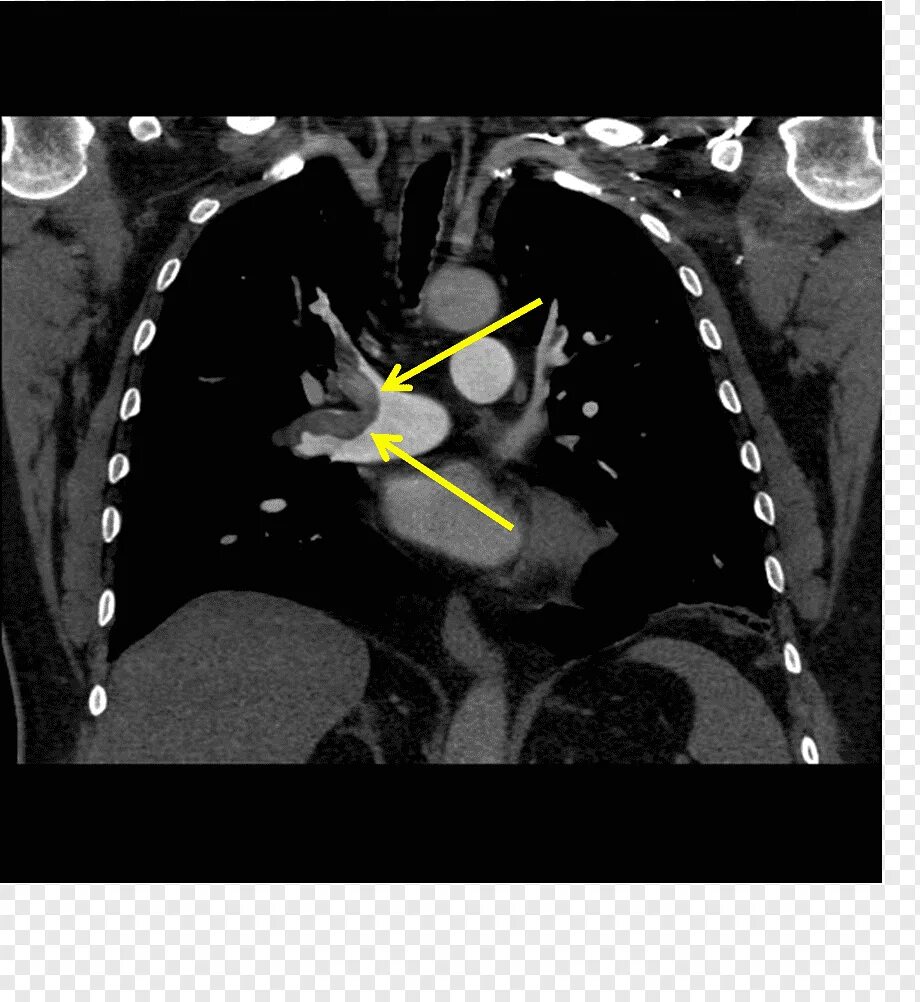

Легочный ствол на кт